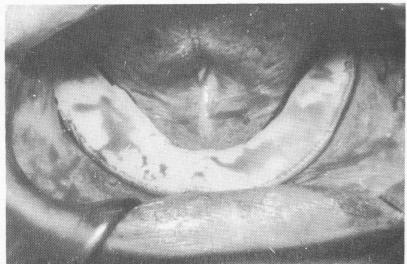

When the wound has been closed, an intraoral bandage* may be set over it to speed healing (Fig. 12-22). In addition to protecting the wound, the bandage provides medication. To make the bandage, a portion is cut to fit over the entire wound area. The paper covering the adhesive is removed and the bandage positioned and held for about 30 seconds. The adhesive contains hydrophilic compounds that hold the bandage in place from 6 to 12 hours. If possible, it is better to leave the bandage in place 24 hours.

Fig. 12-22. An intraoral bandage (E. R. Squibb and Sons) is sometimes used directly over the sutured tissue.

2 Intraoral bandage used directly over the sutured tissue